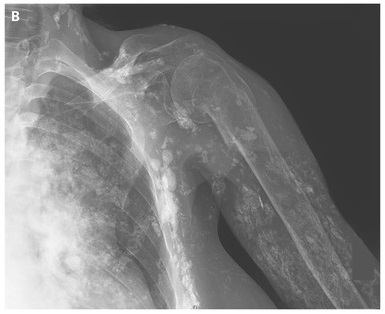

A radiograph of the left shoulder showed extensive soft-tissue calcification and an old fracture of the surgical neck of the humerus, which was attributed to glucocorticoid-induced osteoporosis.

The clinical presentation was consistent with a diagnosis of dermatomyositis-associated calcinosis. In addition to its association with dermatomyositis, soft-tissue calcinosis can be seen in other connective-tissue disorders, such as systemic sclerosis (scleroderma). The calcifications progressed during treatment with infliximab.